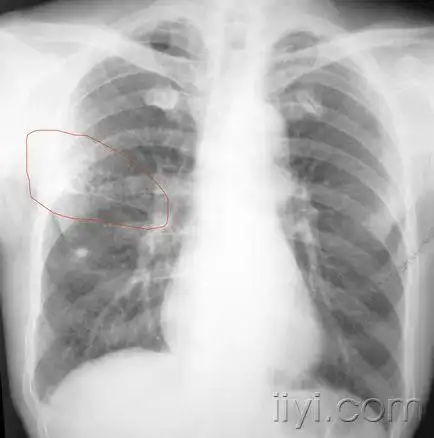

少见病例,病史资料全,蜂窝肺,高手来帮着诊断一下.

【病例讨论】蜂窝肺改变-迁延3个月,抗生素应用仍不见好转

【讨论】左肺蜂窝状改变84289【随访反馈】